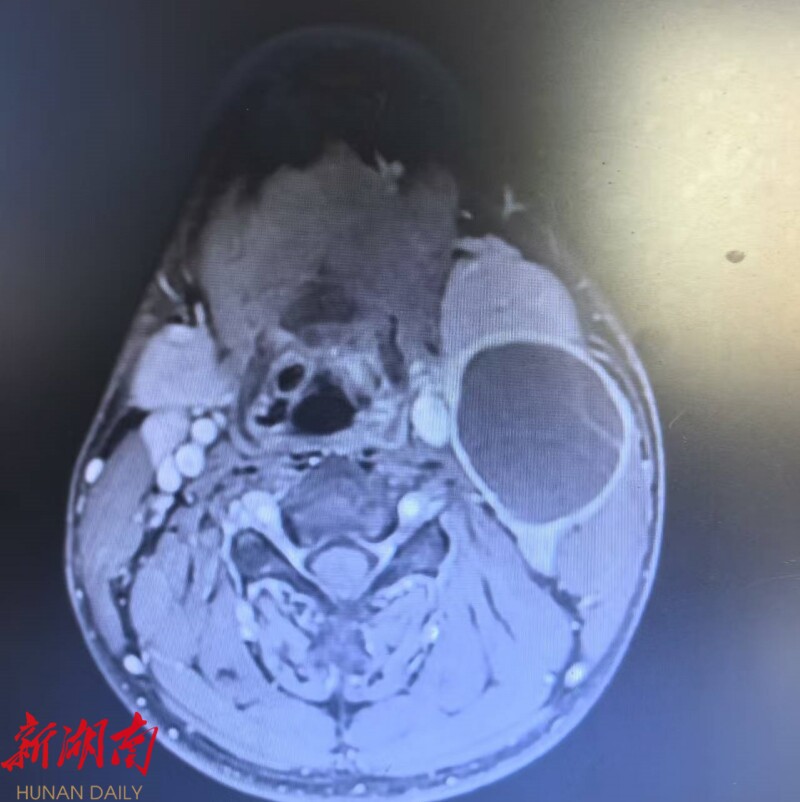

患者曹某,17岁,因发现颈部左侧无痛性肿块10余天,且近期感觉吞咽不适与声音嘶哑前来就诊。经检查,发现其左侧颈动脉有一大小约5.5×3.8cm的囊性占位性病变。影像学显示,肿瘤位置极深,与颈内动脉、颈外动脉关系密切,与迷走神经、舌下神经等重要结构粘连严重,手术难度和风险极大。

面对挑战,耳鼻咽喉头颈外科团队进行了周密的术前准备。利用三维重建技术精准还原了肿瘤与周边血管、神经的立体关系,并制定了详尽的手术预案及应急措施。